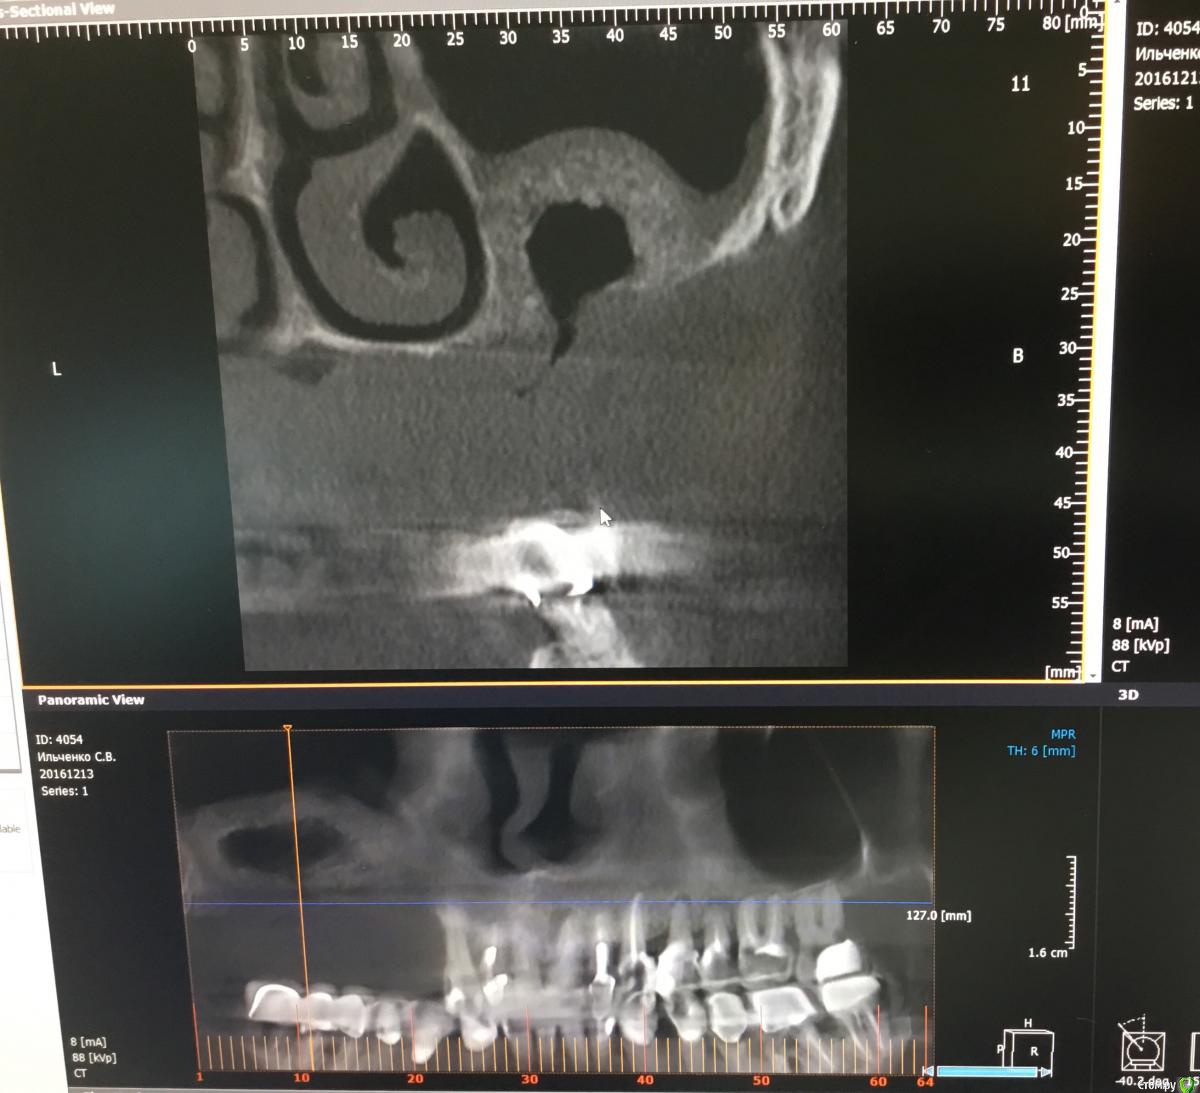

kriokov Опубликовано 17 января, 2017 Поделиться Опубликовано 17 января, 2017 Bier, Вы можете реформат панорамы залить, чтобы по позициям ясно было. Ширину увеличивали тоже? Ссылка на комментарий

Bier Опубликовано 17 января, 2017 Автор Поделиться Опубликовано 17 января, 2017 КТ на работе, ширину увеличивал в области клыковадентия 15-12, 22-25 2 Ссылка на комментарий

kriokov Опубликовано 17 января, 2017 Поделиться Опубликовано 17 января, 2017 (изменено) КТ на работе, ширину увеличивал в области клыков адентия 15-12, 22-25как думаете, почему не весь графт отработал? На установке болтов окно после синуса "окостенелое" было? Изменено 17 января, 2017 пользователем kriokov Ссылка на комментарий

Bier Опубликовано 17 января, 2017 Автор Поделиться Опубликовано 17 января, 2017 как думаете, почему не весь графт отработал? На установке болтов окно после синуса "окостенелое" было?потому что произошла неполная отслойка слизистой пазухи во время операции. Она подвернулась или расслоилась. 1 Ссылка на комментарий